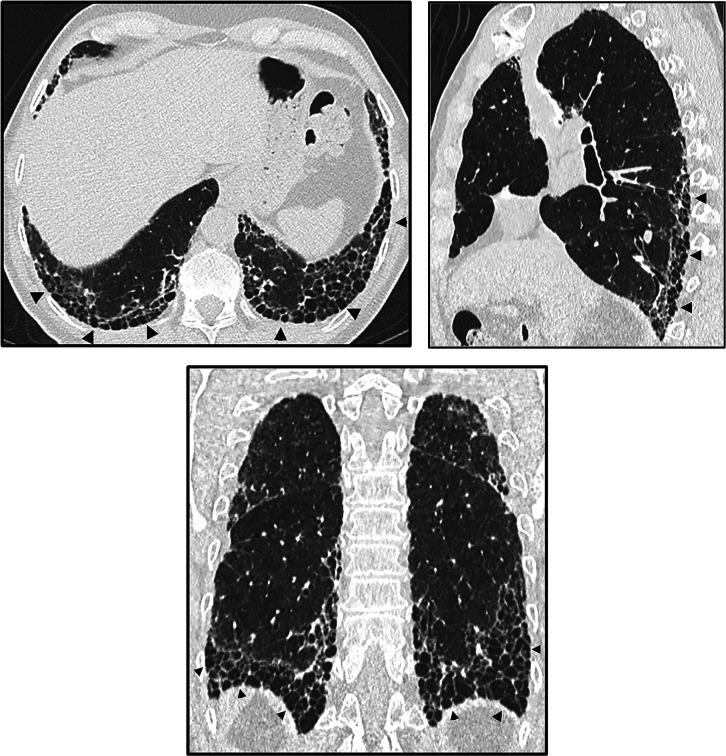

This American Thoracic Society, European Respiratory Society, Japanese Respiratory Society, and Asociación Latinoamericana de Tórax guideline updates prior idiopathic pulmonary fibrosis (IPF) guidelines and addresses the progression of pulmonary fibrosis in patients with interstitial lung diseases (ILDs) other than IPF. A committee was composed of multidisciplinary experts in ILD, methodologists, and patient representatives. ) Update of IPF: Radiological and histopathological criteria for IPF were updated by consensus. Questions about transbronchial lung cryobiopsy, genomic classifier testing, antacid medication, and antireflux surgery were informed by systematic reviews and answered with evidence-based recommendations using the Grading of Recommendations, Assessment, Development and Evaluation (GRADE) approach. ) Progressive pulmonary fibrosis (PPF): PPF was defined, and then radiological and physiological criteria for PPF were determined by consensus. Questions about pirfenidone and nintedanib were informed by systematic reviews and answered with evidence-based recommendations using the GRADE approach. ) Update of IPF: A conditional recommendation was made to regard transbronchial lung cryobiopsy as an acceptable alternative to surgical lung biopsy in centers with appropriate expertise. No recommendation was made for or against genomic classifier testing. Conditional recommendations were made against antacid medication and antireflux surgery for the treatment of IPF. ) PPF: PPF was defined as at least two of three criteria (worsening symptoms, radiological progression, and physiological progression) occurring within the past year with no alternative explanation in a patient with an ILD other than IPF. A conditional recommendation was made for nintedanib, and additional research into pirfenidone was recommended. The conditional recommendations in this guideline are intended to provide the basis for rational, informed decisions by clinicians.

美国胸科学会、欧洲呼吸学会、日本呼吸学会和拉丁美洲胸科学会更新了特发性肺纤维化(IPF)指南,涵盖了除 IPF 以外的间质性肺疾病(ILD)患者肺纤维化的进展。一个委员会由ILD 的多学科专家、方法学家和患者代表组成。

• 更新 IPF:通过共识更新了 IPF 的放射学和组织病理学标准。关于经支气管肺冷冻活检、基因组分类器检测、抗酸药物和抗反流手术的问题,通过系统评价提供信息,并使用基于证据的推荐和 Grading of Recommendations, Assessment, Development and Evaluation (GRADE) 方法回答。

• 进行性肺纤维化(PPF):定义了 PPF,然后通过共识确定了 PPF 的放射学和生理学标准。关于吡非尼酮和尼达尼布的问题,通过系统评价提供信息,并使用基于证据的推荐和 GRADE 方法回答。

• PPF:PPF 定义为在过去一年中,在非 IPF 的ILD 患者中,出现至少三个标准中的两个(症状恶化、放射学进展和生理学进展),且无其他解释。建议使用尼达尼布,并建议对吡非尼酮进行进一步研究。